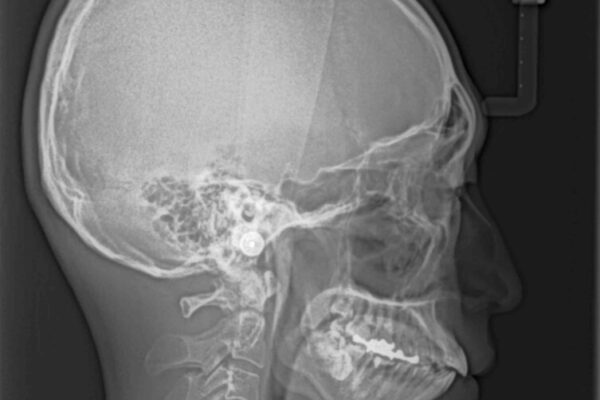

精密検査の結果、上下左右の小臼歯4本を抜歯し、そのスペースに前歯を後方へ移動させる矯正治療をご提案しました。

治療前

• 口元の突出感を改善!目立ちにくいワイヤー矯正で自信を持てる自然な横顔に 治療前画像